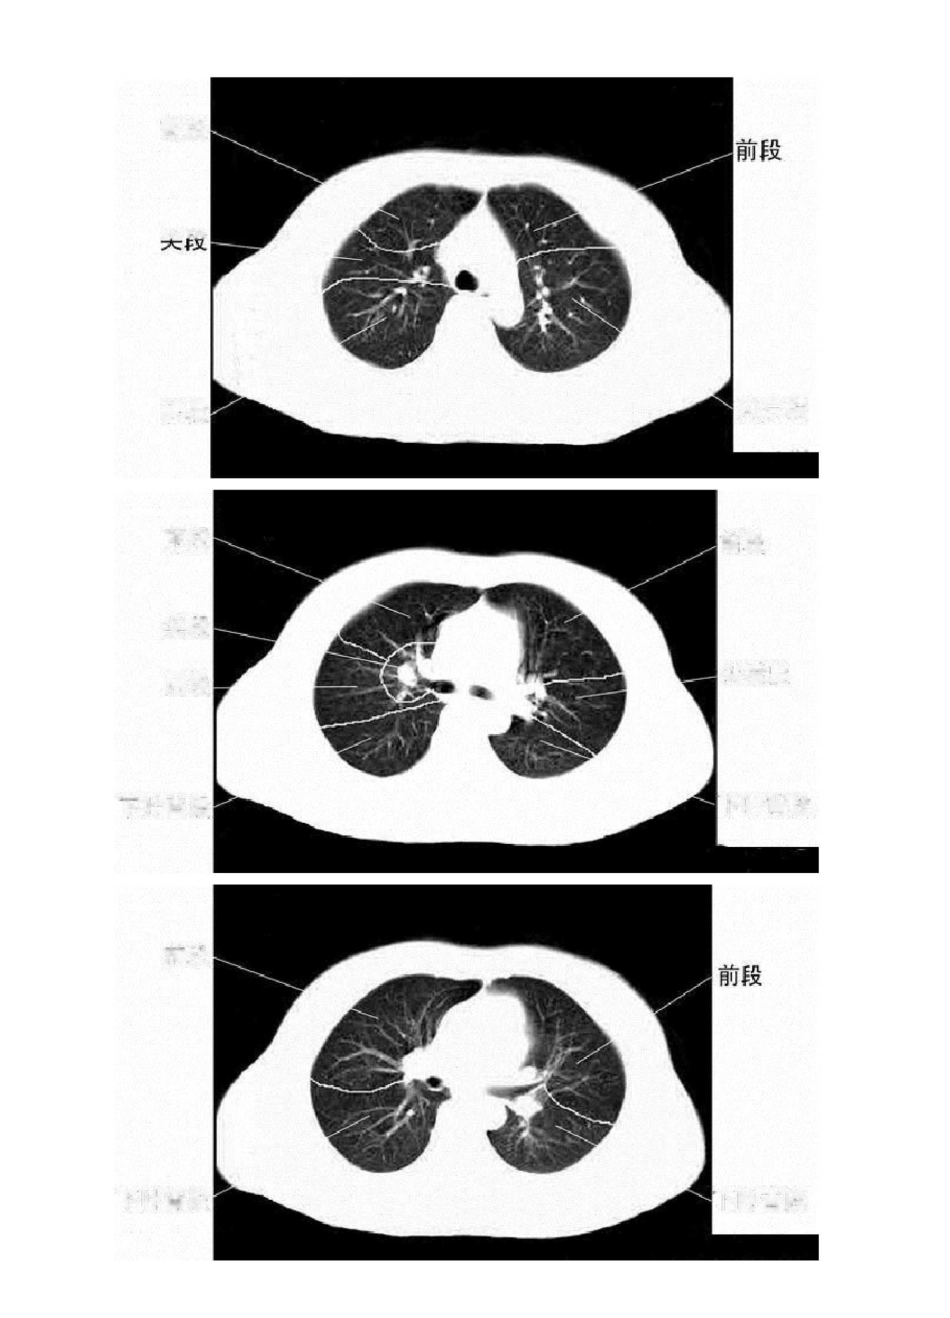

胸部 CT 肺段划分口诀独眼能看双上肺,左下还留一点背。对眼能看前后背,双眼能看前和背。嵴角出现能看中舌背,基底干出现就看余下肺。“独眼能看双上肺,左下还留一点背”:指气管层面,能显示两上肺,在偏下方层面,能看到左肺下叶背段“对眼能看前后背”:在支气管分叉层面(T4 以下)能看到两肺上叶前、后段及两肺下叶背段"双眼能看前和背":双眼与对眼都是指左右主支气管,“对眼”指左右主支气管距离近,"两眼"是气管分叉下方层面及肺动脉层面,左右支气管距离较远,此时断面图像上只能显示上叶前段和下叶背段"嵴角出现能看中舌背":嵴角指有中叶支气管与下叶支气管的夹角,内有右上肺静脉的断面,此层面能看到右肺中叶,左上肺舌叶及两肺下叶背段“基底干出现就看余下肺”:两下叶支气管分出基底段时能观察中叶,舌叶及两肺下叶各基底段,所以觉得此句应改为“基底干出现就看中舌余下肺”图解如下:前段i\xrn.尖后段后段前段前段尖段尖后段后段下叶背段下叶背段前段下叶昔段下叶背段內侧段夕卜侧段前基底段外基底段后基底段内基底段下叶背段下叶背段前段前段上舌段外侧段前基底段外基底段后基底段内侧段下舌段内前基底段外基底段右肺上叶右侧斜裂右肺下叶背段左肺上叶左侧斜裂左肺下叶背段右肺中叶右侧斜裂右肺下叶左肺上叶舌段左侧斜裂左肺下叶右肺上叶水平裂少血管带'右肺下叶左侧斜裂少血管带右肺上叶水平裂少血管带右侧斜裂右肺下叶左肺上叶左侧斜裂少血管带水平裂顶部右侧斜裂左主支气管右上叶尖段支气營右上叶支气管右上叶肺静脉后支左上叶尖后段支气管右主支气管 _ 左主支气管左肺动脉右主支气管支气營右下肺动脉干中间段支气管左肺上静脉左上叶舌毀支气管右肺中时动脉右中叶支气管右下肺动脉右下支气管咅下支气管左下肺动脉前内基底支左下肺动脉后外基底支左肺下静脉后右下叶内基底脱支气管右下肺动脉右下叶支气管右肺下静脉左肺下静脉左下肺内前基底段动脉左下叶内前基底駁支气管左下叶后基底